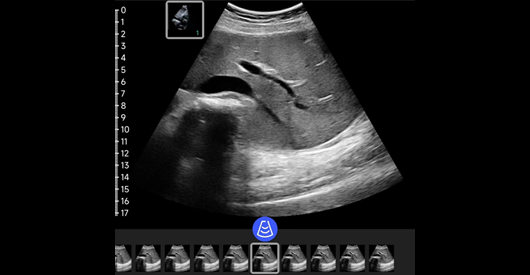

肾脏

探头类型:凸阵探头。典型场景:肝胆胰脾肾。